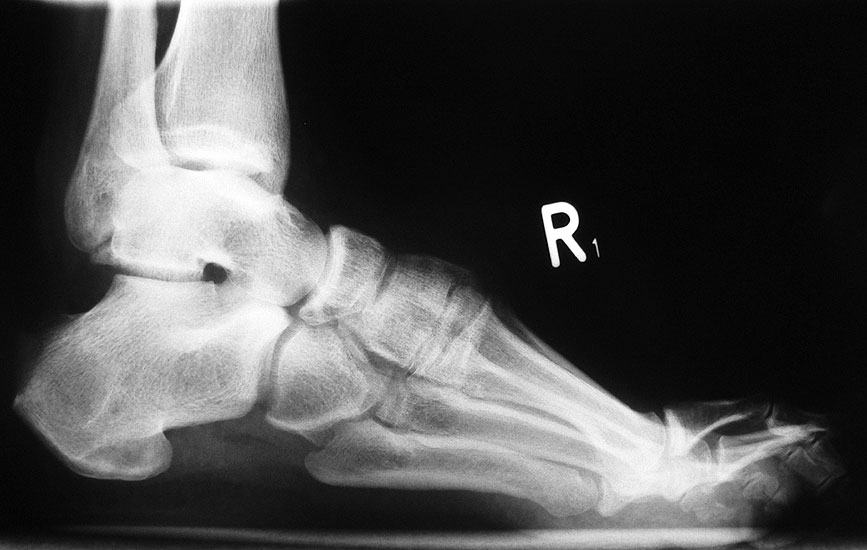

• Fuß belastet dp und seitlich (Abb. 14 und 15)

• Saltzman view (Abb. 16)

Typische Merkmale der Standard-Seitaufnahme des Fußes im Stand

• Knöchelgabel ist außen rotiert

• Talus und Calcaneus verlaufen fast parallel

• Sinus tarsi ist einsehbar

• Subtalare Gelenklinie verläuft horizontal und ist breit einsehbar

• Der Abstand Malleolus medialis zum Os naviculare ist verkürzt

• Der Calcaneus erscheint verkürzt

• Der Krümmungsscheitel des Fußes ist erhöht

• Calcaneus pitch ist meist erhöht, der Rückfuß Equinus ist eher selten 12